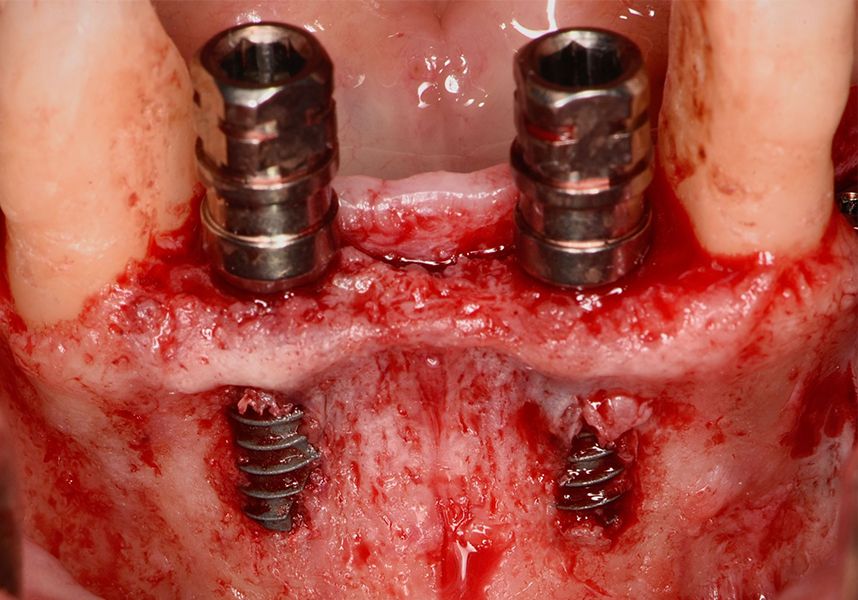

The patient was anesthetized and a flap was made from the distal area of tooth 43 up to 36. Then two Avinent Biomimetic Ocean IC implants of 3.5x10 were inserted in positions 32 and 42.

Respecting the three-dimensionally correct position of the implant led to bone fenestration, leaving the apical part of the apex of the implant exposed almost to the mid-point of its length at 42 and a third in 32.

To treat the defect, bone regeneration was carried out simultaneous to the surgical process, with an autologous bone graft from the patient. In the internal part of the graft we used autologous cortical bone obtained by scraping (Safescraper) and from the biological drilling, at low revolutions and without irrigation, from the other implant beds. In the external layer of the regeneration we used a xenograft (Genoss, Osteogenos) and this was covered with a reabsorbable collagen barrier membrane (Evolution STD, Osteogenos).

The membrane was sutured with PGA reabsorbable suture to the periosteum to secure it, thus avoiding subsequent reentry to remove fixings such as tacks.